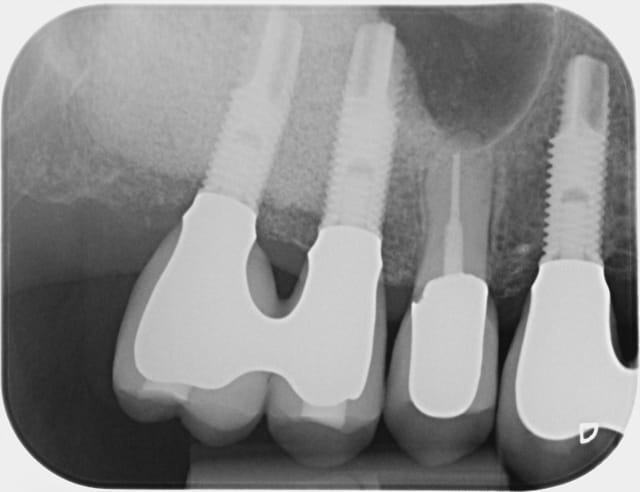

Bon alors revenons a cette 15.

On voit bien sur l'historique radio que la migration apicale a débuté entre janvier et mai 2014. Date à laquelle j'ai dû changer la 14.

A 10 mars 2008 hjqdhq - Eugenol

B 22 mai 2009 fhhmrm - Eugenol

C 04 juin 2009 vjcx5r - Eugenol

D 15 juin 2009 od7vwg - Eugenol

E 25 juin 2009 hht4ji - Eugenol

F 18 novembre 2009 hhywkg - Eugenol

G 21 janvier 2011 xurlrw - Eugenol

H 19 fevrier 2013 tvy4db - Eugenol

I  21 janvier 2014 gyys5o - Eugenol

J 21 mai 2014 i8zdgv - Eugenol

Jj 16 octobre 2014 clat7g - Eugenol

Jjj 16 otobre 2014 yevkyg - Eugenol

K  6 novembre 2014 lfkxbg - Eugenol

L  6 novembre 2014 gcsqeq - Eugenol

M  6 novembre 2014 gc5q3z - Eugenol

P  6 novembre 2014 cy54gy - Eugenol

Q  6 novembre 2014 vtispk - Eugenol

R  6 novembre 2014 nrhlqf - Eugenol